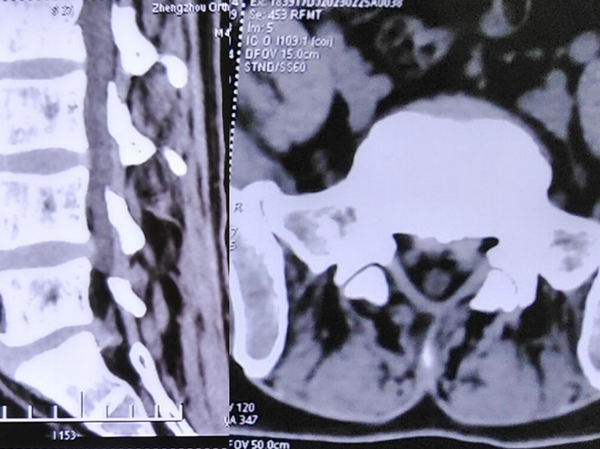

术前检查

检查提示腰5/骶1椎间盘向左后脱出,脊髓神经受压明显。骨科一病区徐明杰主任、王三木医师团队认真诊查病人,认为患者存在腰5/骶1椎间盘向左后脱出并椎管狭窄,保守治疗差,需要手术扩大狭窄的椎管并摘除突出的腰椎间组织解除神经受压,适合采用UBE技术为患者进行手术治疗。术前,徐明杰主任团队制定了严密的手术治疗方案,并与患者及家属充分、细致沟通。